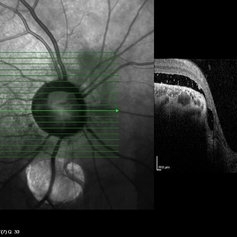

Coloboma of Optic Disc

Coloboma of Optic Disc

Sep 23 2022 by Kavya Rao, M.S

OCT and OCT Angiography (4.5x4.5mm)(ZEISS) of 39-year old man ,came for routine check up and diagnosed with coloboma of Optic Disc in the Right Eye as an incidental finding.

Photographer: Dr.KAVYA RAO, LIONS CLUB OF HYDERABAD, SADHURAM EYE HOSPITAL,HYDERABAD,INDIA

Condition/keywords: coloboma